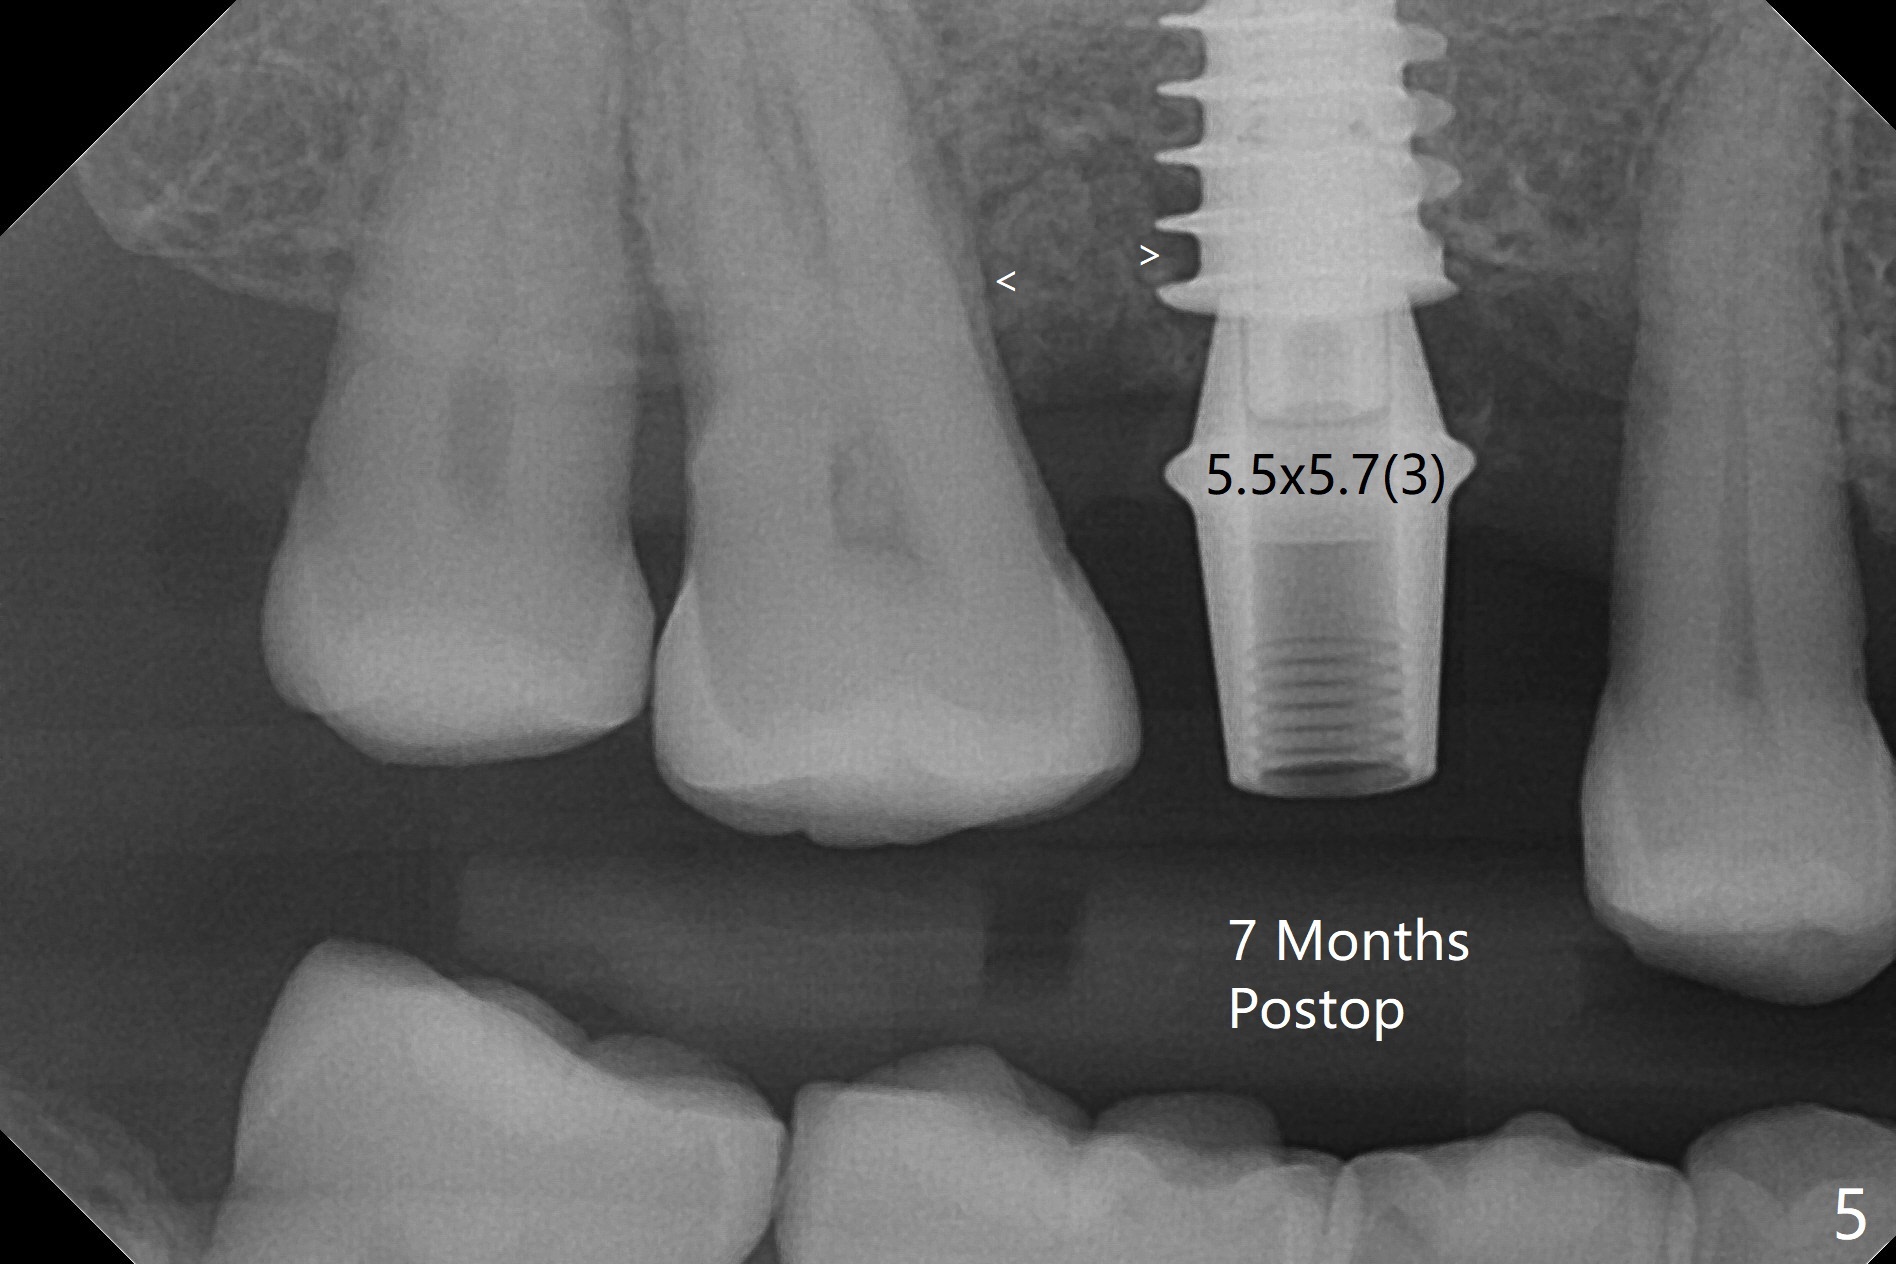

After extraction and debridement, osteotomy is initiated in the mesiobuccal socket free hand. Since the remaining bone is ~ 2 mm, the sinus floor is perforated suddenly. Fortunately the sinus membrane is not, as related to its thickening (similar to water ballooning, without symptom). Use 2-3.5 mm drills to enlarge the bony perforation (mainly lateral movement), followed by pushing bone graft upstairs with a curette (Fig.1 *); insert a 4x9 mm dummy implant (Fig.1) to determine the length of the final implant (Fig.2,3). A drawback of this case is the low torque (<20 Ncm), considering the thin bone. Following deeper implant placement, a 5.2x6(2) mm temporary abutment is placed for an immediate provisional to keep large amount of bone graft in place (Fig.3 *). There is no pain 1 week postop, while the immediate provisional remains stable partially because of the temporary abutment (Fig.4 ^). Four months postop, the temporary crown is loose. After removal of the temp and the temp abutment, gingival cuff is erythematous. A 6x4 mm healing abutment is placed. The bone graft (Fig.3 *) appears to have attached to the root of the neighboring tooth and the implant threads 7 months post op (COVID 19, Fig.5 arrowheads)). The bone graft appears to continue to merge with the neighboring root, bone and implant 10 months postop (2.5 months post cementation, Fig.6). The bone graft in the sinus seems to collapse and condense 10 months postop (Fig.7 *).